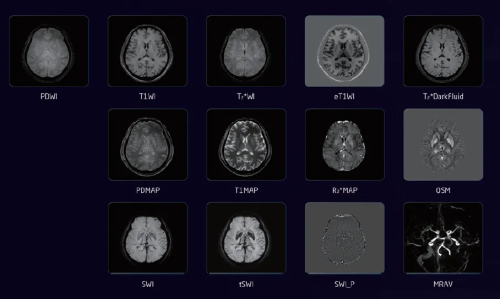

Fast BrainQuant 定量一键脑成像

基于3D GRE序列,实现一次扫描多对比定量成像,涵盖常规结构图像、定量图像以及血管图像,革新磁共振扫描模式,助力精准脑科学研究。